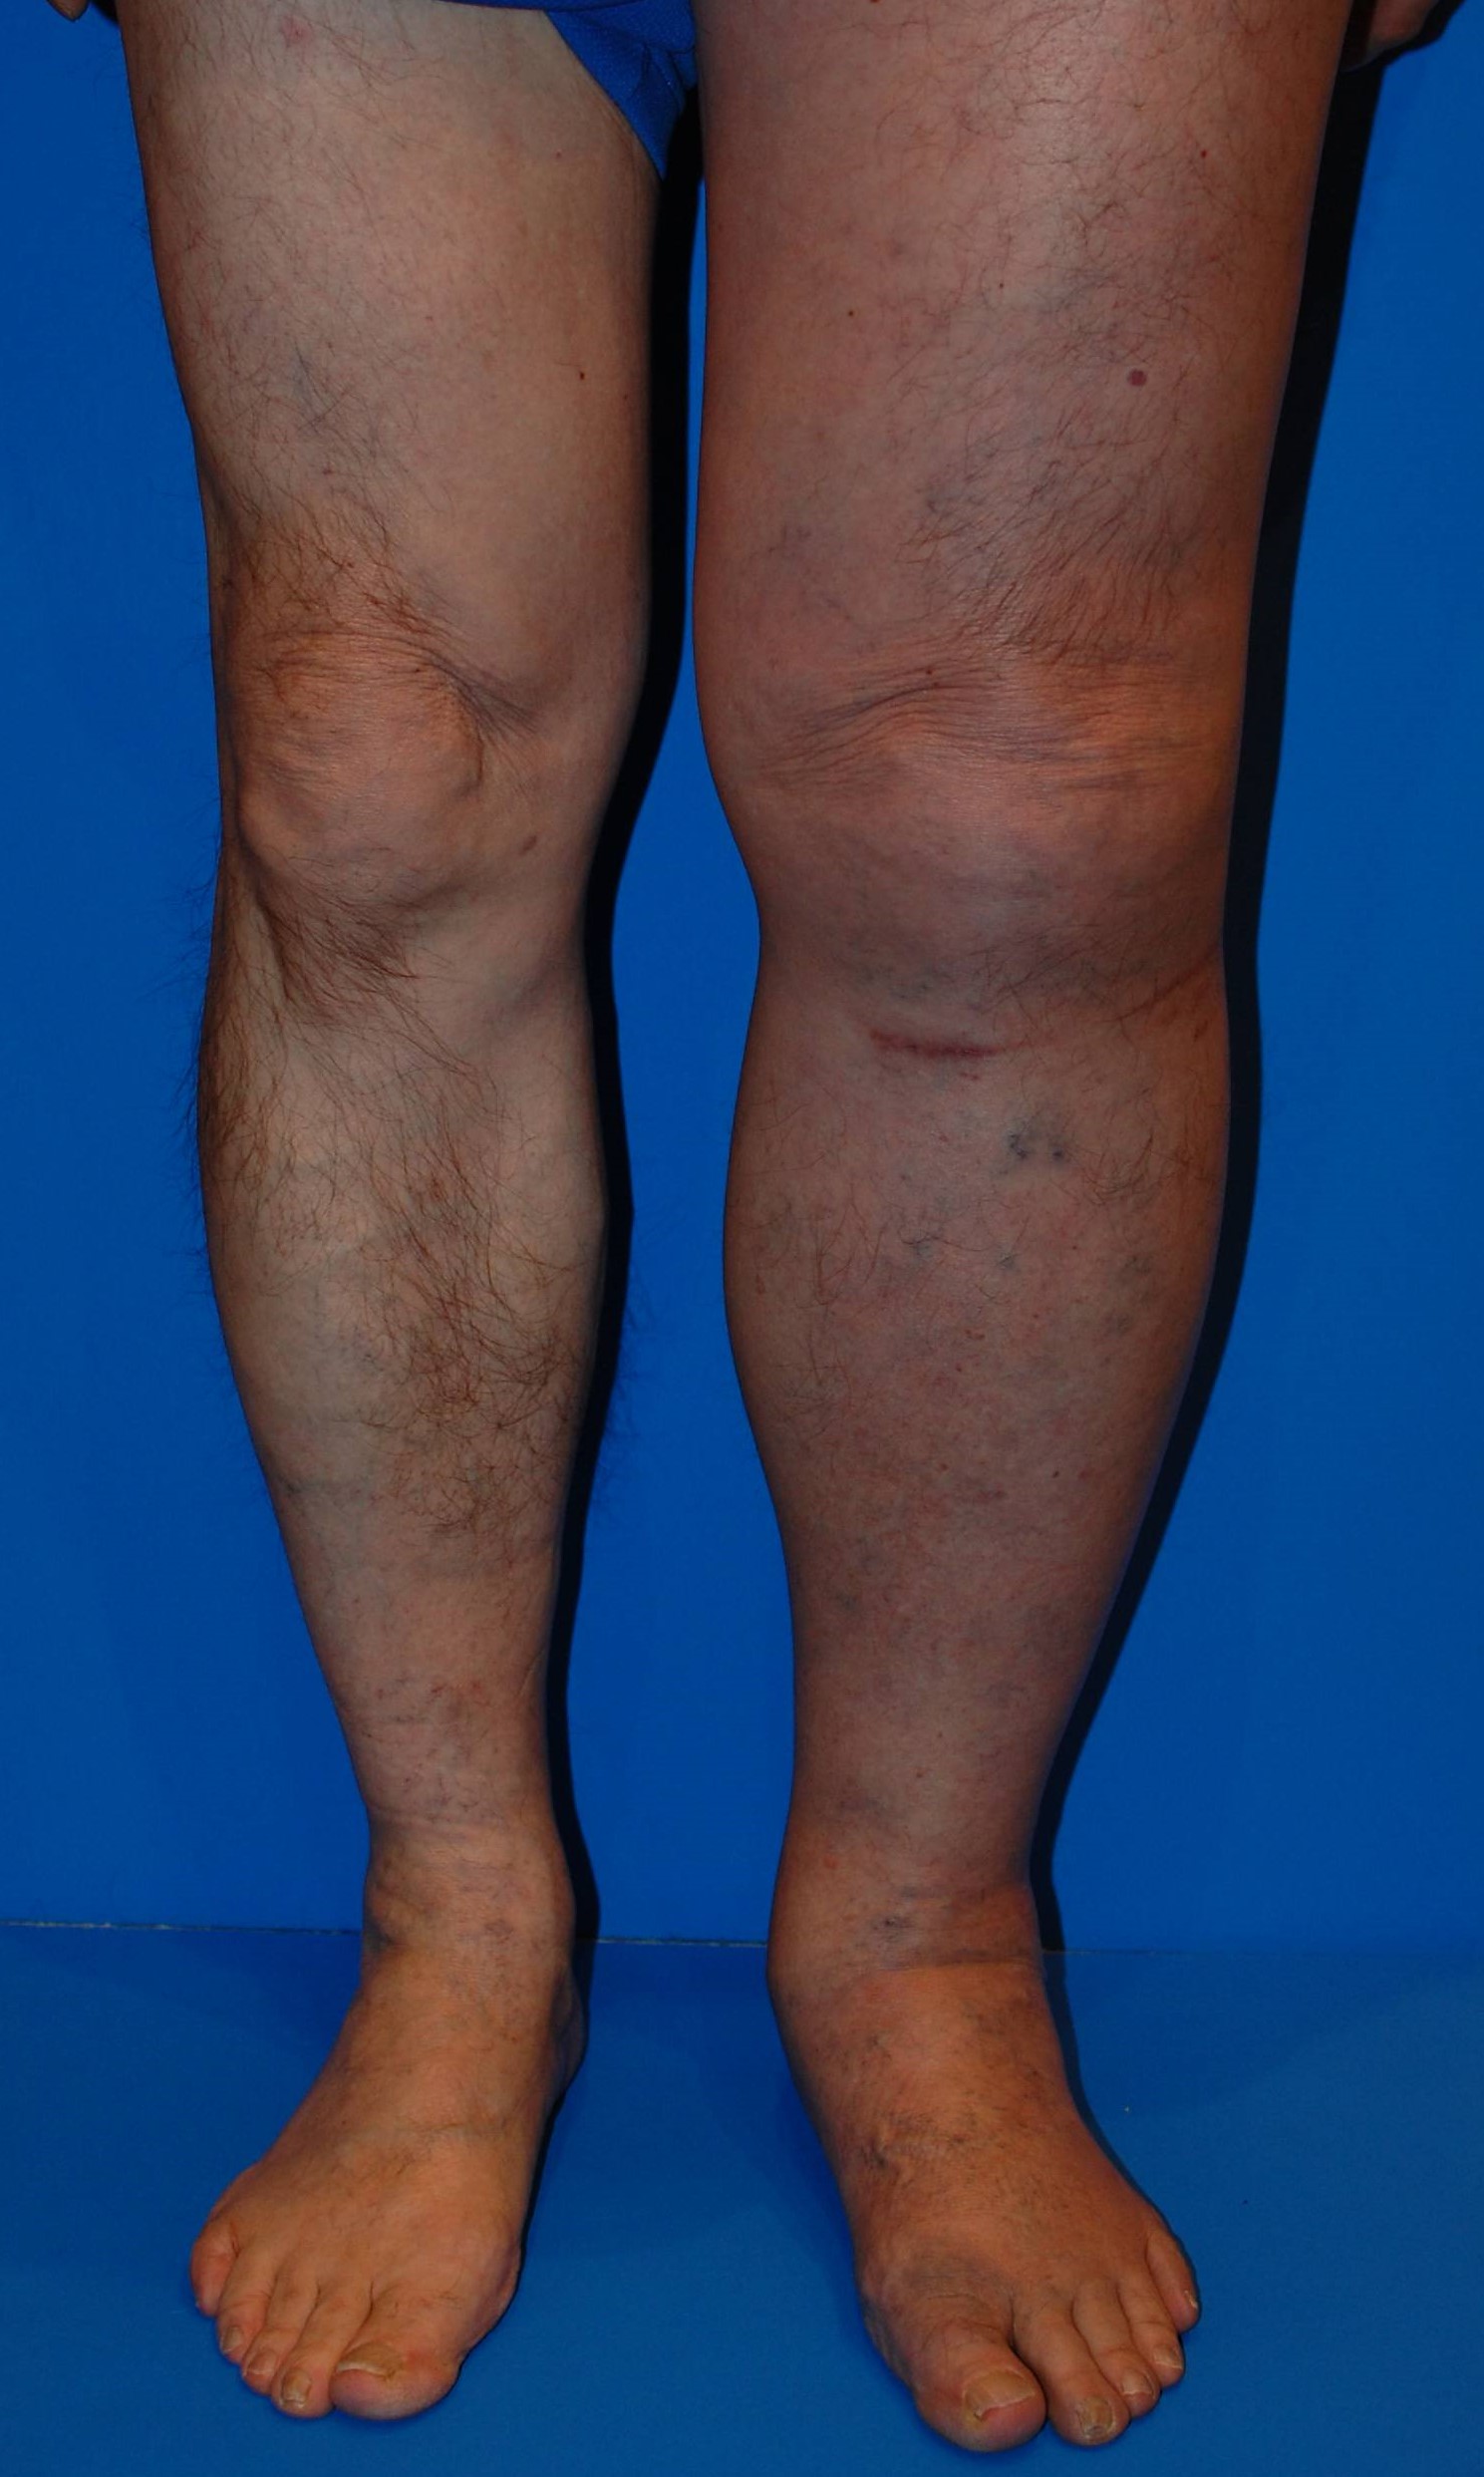

すでに下肢静脈瘤で足の血管がボコボコと浮き出ている方は、

血栓を繰り返す前に手術を検討することも重要です。

下肢静脈瘤 画像

下肢静脈瘤を根本的に治療することで、血栓性静脈炎や重篤な合併症のリスクを下げることができます。